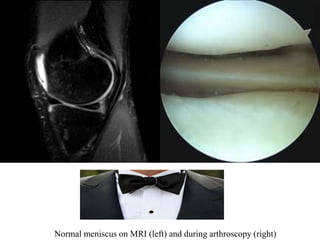

Normal meniscus on MRI (left) and during arthroscopy (right)

Normal meniscus onMRI (left) and during arthroscopy (right)

• #23 Normally the medal and lateral menisci appear as low signal bow-tie-shaped structures between the femoral condyles and tibial plateauxThe absent bow tie sign represents the loss of the normal appearance of the menisci on parasagittal MRI images, and is suggestive of meniscal injury.